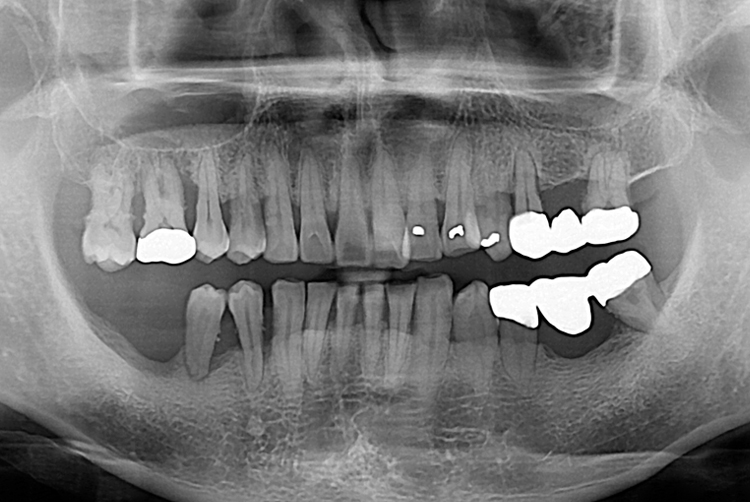

하영준_후.jpg

치료후 : 2017-11-30

세종치과는 많은 환자와 다양한 케이스를 바탕으로 항상 편안한 임플란트 수술을 제공하고자 노력하고,

오래동안 튼튼히 쓸 수 있는 임플란트 수술을 가장 큰 목표로 삼고 있습니다.